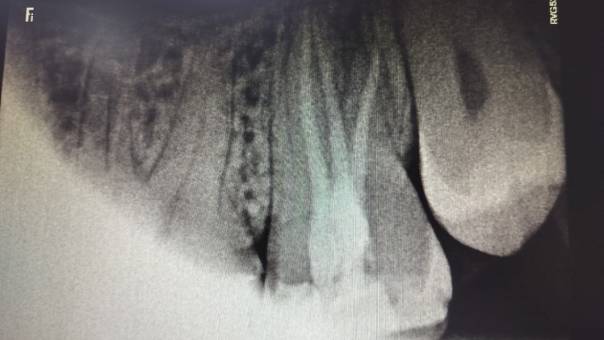

Our Treatment Approach:

After discussing the findings with the patient, we

recommended a Re-RCT, focusing on the missed distal

canal. This would allow us to eliminate the

infection and restore the tooth’s health.

Clinical Outcome:

The procedure was done comfortably and successfully

on the patient, and recovery was smooth. At

follow-up visits, he reported complete relief from

pain, and healing was progressing as expected.

Locating the distal canal

After Obturation